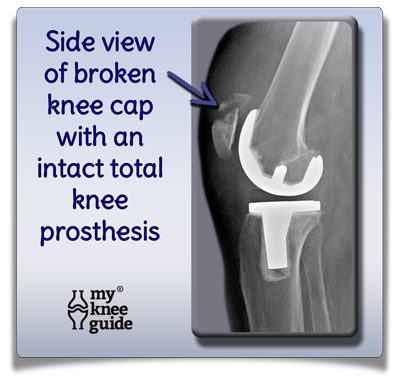

Product code: Broken knee cap after knee replacement store

Broken knee cap after knee replacement store